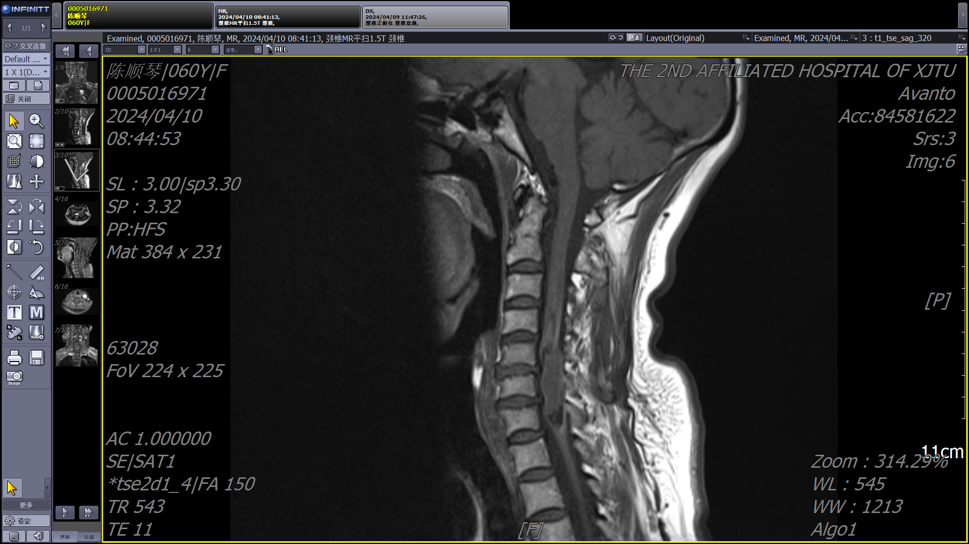

患者为一名中年女性,因颈部疼痛和四肢麻木症状就医,颈椎MRI检查结果显示颈4-7椎管内存在异常信号。由于病变位于颈段脊髓,手术风险极高,稍有不慎就可能导致瘫痪,多家医院的医生都遗憾地表示没有能力“接招”。